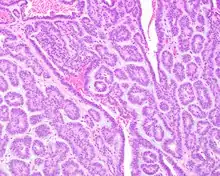

Canalicular adenoma growths are usually small at the time they are noticed, with an average size of about 1.6 cm.[1] Their histologic appearance is very distinct, with a channel-like pattern between cords and ribbons; the pattern has been described as resembling a "string of pearls."

The growths often contain are often small bight squamous balls, or morules. They also tyipcally contain a well-developed supporting tissue - a fibrous stroma - which is rich in hyaluronic acid and chondroitin sulphate.[1] In a few cases, the growths may contain small calcium deposits or microliths. Although it is seldom necessary, a pathologist can confirm the existence of canalicular adenoma through immunohistochemistry studies, with the cells reacting with pancytokeratin, S100 protein and SOX10, with a delicate GFAP reaction around the periphery.[5][1][6][7] Although it is a benign tumor, a positive diagnosis of canalicular adenoma may be necessary to exclude the existence of other medical conditions such as a basal cell adenoma, pleomorphic adenoma, adenoid cystic carcinoma, and polymorphous adenocarcinoma.